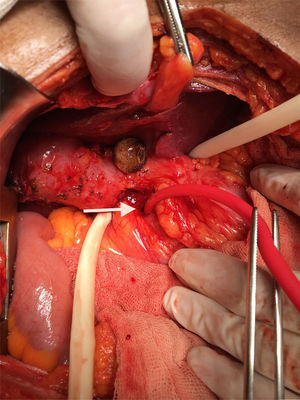

A 57-year-old man with an unremarkable past medical history complained of moderately intense localized pain in the epigastrium after eating solid foods, and later after drinking liquids. The accompanying nausea and vomiting caused important fluid and electrolyte imbalance, for which he was hospitalized. Laboratory tests and imaging studies were ordered and chronic cholecystitis with gallstones was diagnosed through ultrasound imaging (USG). A lesion infiltrating into the first portion of the duodenum and an ulcer were identified at endoscopy and at esophagogastroduodenography (EGD) (fig. 1). A computed axial tomography scan showed gas in the gallbladder and thickening of the gastric antrum and the duodenal bulb walls (figs. 2 and 3). Tumor markers were in the normal range. The patient underwent exploratory laparotomy that revealed chronic inflammation of the gall bladder, cholecystoduodenal fistula with loss of the normal anatomic arrangement, and annular pancreas (figs. 4 and 5) that did not compromise the integrity or permeability of the duodenum. Cholecystectomy was performed, the fistula was dismantled, and primary closure of the duodenum was carried out. The patient progressed favorably and is currently under follow-up at the hepatopancreaticobiliary surgery clinic.